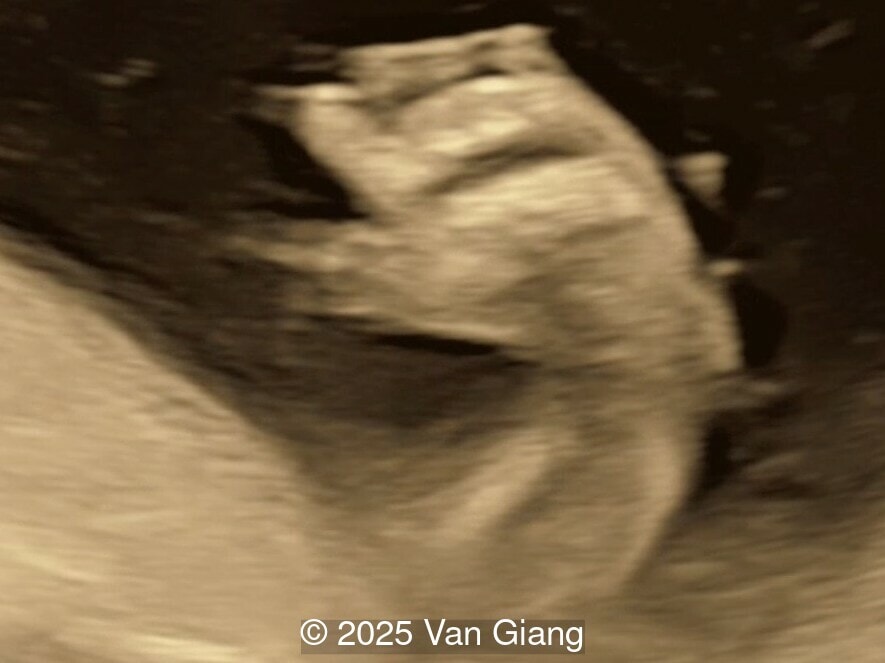

Image 3

Ultrasound revealed severe mandibular and zygomatic hypoplasia, glossoptosis, cleft palate, and micrognathia with an abnormal facial profile. Both upper limbs showed radial ray sequence with abnormal thumbs and shortened forearms. Unilateral clubfoot was also noted. No major cardiac or visceral anomalies were observed. Based on these findings, Nager syndrome was suspected.

Unilateral clubfoot

Image 5 Unilateral clubfoot